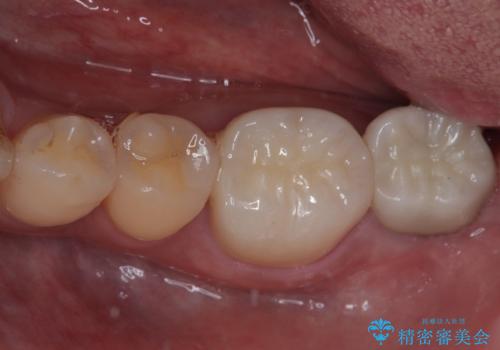

- 左下の歯が欠けてしまったとのことで来院された患者様です。

大きな銀歯が装着されており、その周りからむし歯が広がっている状態でした。

特に症状はなく、神経組織も健全な状態であったため、むし歯を全て取り切った後にフルジルコニアクラウンにて補綴することとしました。